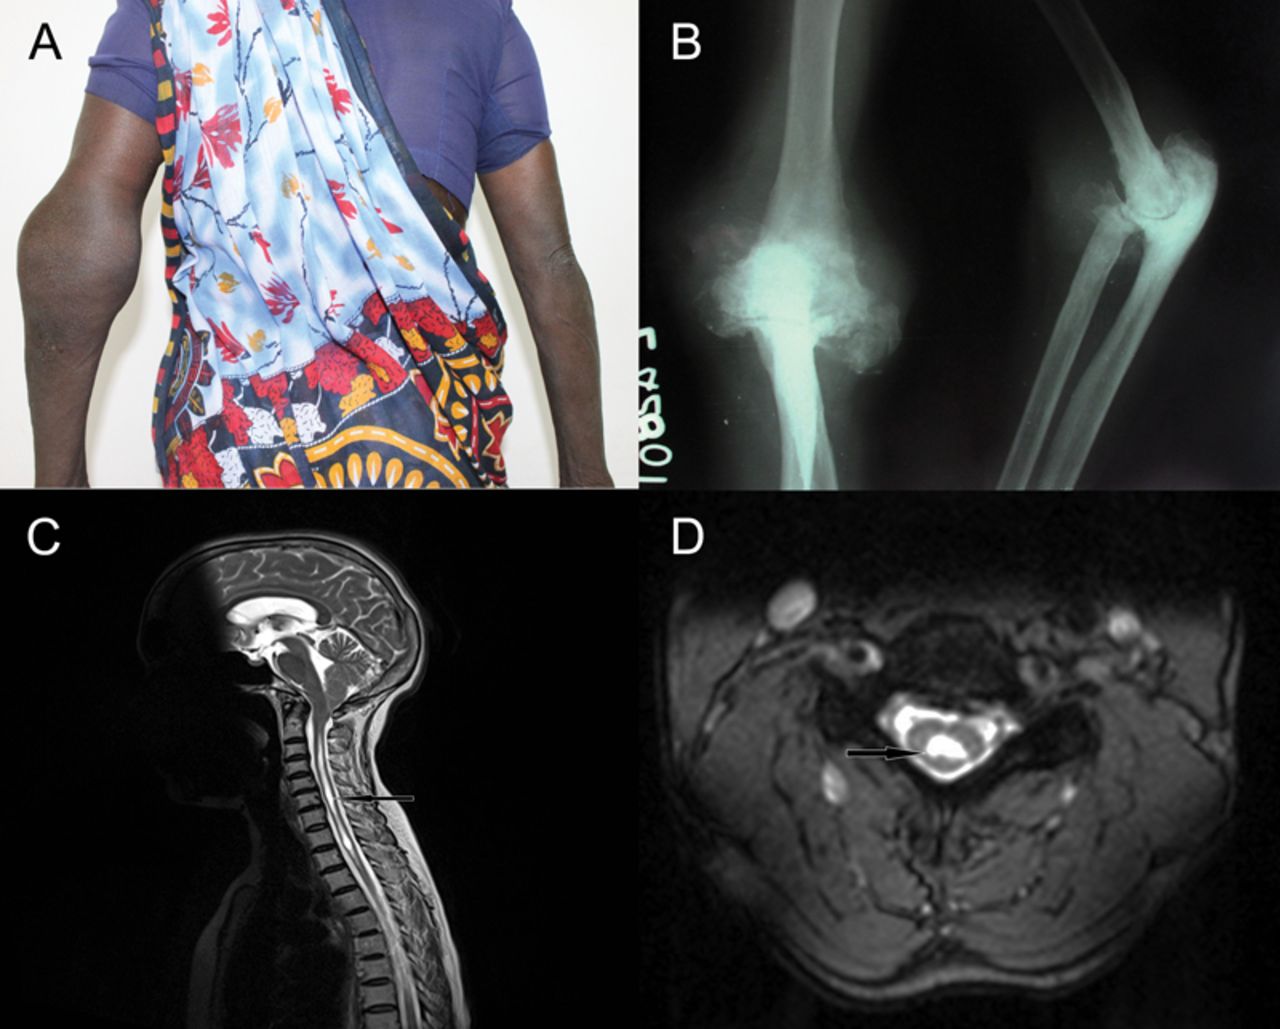

一个45岁的女人面对左肘肿胀和最小疼痛3个月(图)。她不记得任何上肢损伤。考试,她的左肘关节炎,浪费手的小肌肉群的,抑郁的肱二头肌和旋后肌抽搐,减少疼痛和温度感觉C5 T1影响双边。测试梅毒、糖尿病和麻风病是负面的。左肘x射线显示关节破坏、瓦解、硬化和碎片的形成(图B),颈椎MRI显示脊髓空洞症从C2 T3椎级别(图C和D)。她被诊断出患有神经性左肘关节病由于脊髓空洞症。1,2

图

颈椎MRI和x射线肘关节

(一)病人的照片显示左肘关节关节炎。(B)左肘关节的x射线显示破坏、瓦解、硬化和碎片的形成暗示神经性关节病。(C)颈椎矢状面MRI t2加权序列显示脊髓空洞症从C2 T3。(D) MRI颈椎轴t2加权序列显示脊髓空洞症在C6水平。